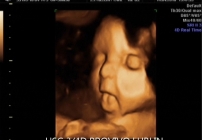

BADANIE USG 3/4D umożliwa dokładny wgląd w rozwój płodu, pozwala na podglądnięcie dziecka w sposób niemalże identyczny z jego aktualnym wyglądem.

W trakcie trwania badania obraz rejestrowany jest na płycie DVD, tak aby każdy przyszły rodzic mógł ponownie odtworzyć badanie w domowym zaciszu. Podczas badania płodu USG 3/4D istnieje również możliwość wydruku zdjęć w formacie kartki pocztowej(148 × 100 mm). Doskonałą jakość, którą charakteryzują się wykonywane przez nas odbitki cyfrowe uzyskujemy dzięki używaniu wyłącznie markowych papierów fotograficznych.